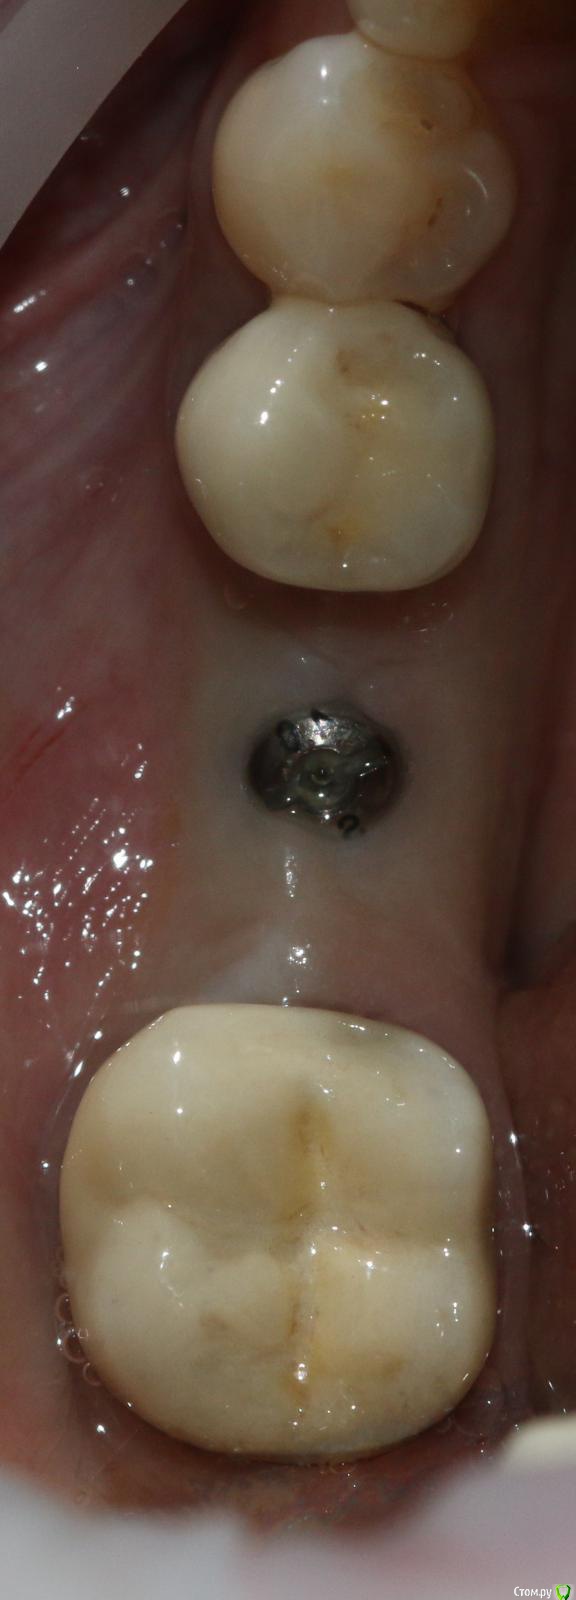

Ильдар Опубликовано 29 марта, 2015 Поделиться Опубликовано 29 марта, 2015 Коллеги, здравствуйте!Вот демонтировал старье. мк на зубы.имплант 4310, поставил поглубже.мк на имплант - техник прислал коронку с шахтой и абатмент,я склеил на fuji1. закрутил на 35 н.залепил не очень красиво , но с плавиковой, силаном и олбонд 3. думаю надежно.контрольный прицельный есть, видимо забыл его. извиняюсь за нечеткие fото. буду рад отзывам 3 Ссылка на комментарий

Ильдар Опубликовано 30 марта, 2015 Автор Поделиться Опубликовано 30 марта, 2015 а зачем?Видимый металл на 6-м это не абатмент, это гирлянда. Граница коронка /абатмент глубже. Поэтому винтовая. Ссылка на комментарий

АнтонТЛТ Опубликовано 30 марта, 2015 Поделиться Опубликовано 30 марта, 2015 чет не понятно у вас винтовая или цементная фиксация? SCRP screw-cement retained prosthesis (цементно-винтовая фиксация) Ссылка на комментарий

Evgeny_K Опубликовано 5 апреля, 2015 Поделиться Опубликовано 5 апреля, 2015 Ильдар, чем пломбировали шахту? Ссылка на комментарий

Ильдар Опубликовано 6 апреля, 2015 Автор Поделиться Опубликовано 6 апреля, 2015 Ильдар, чем пломбировали шахту?Эстелайт оа2 вроде был Ссылка на комментарий